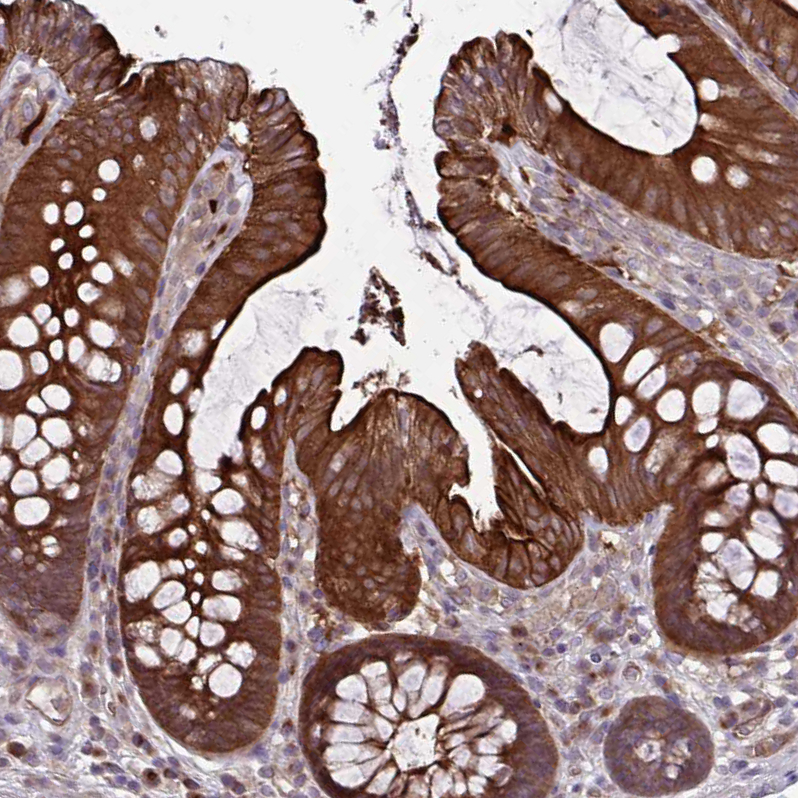

Immunohistochemical staining of human skin shows strong cytoplasmic positivity in squamous epithelial cells.